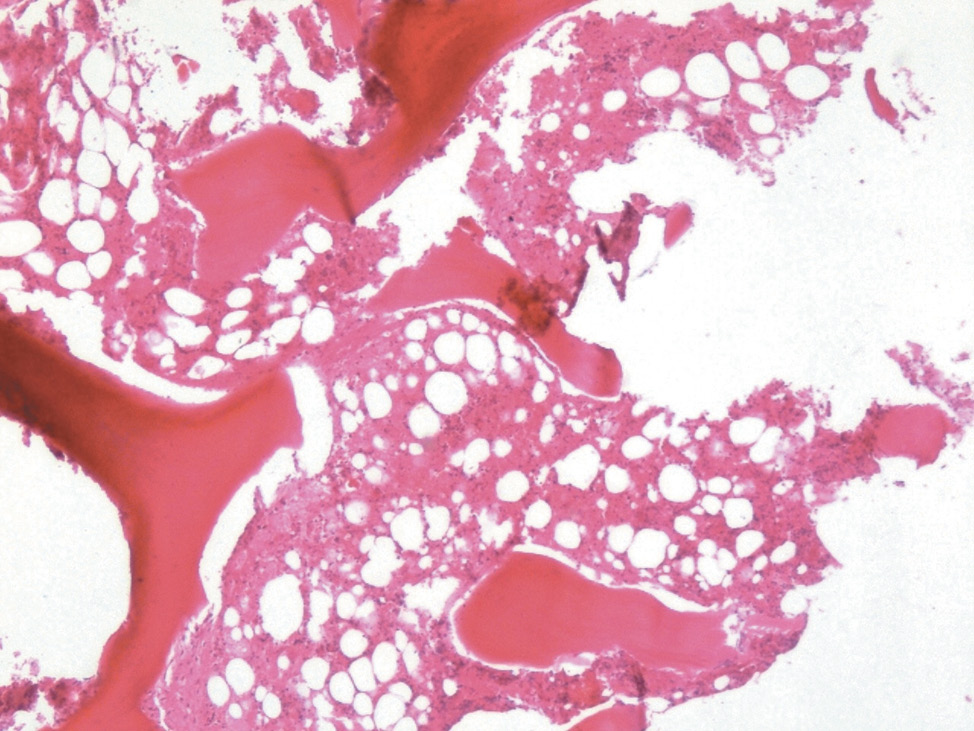

Костный мозг: преимущественно представлен жировой тканью с резким обеднением всех ростков кроветворения (рис. 2, 3).

Рис. 3. Костные балки, костный мозг. ×100, окраска гематоксилином и эозином. Костные балки утолщены, костный мозг преимущественно представлен жировой тканью с резким обеднением всех ростков кроветворения

Fig. 3. Bone rods, bone marrow. ×100, stained with hematoxilin and eosin. Bone rods are thickened. The bone marrow is mostly represented by adipose tissue with a substantial depletion of all the sprouts of hematopoiesis